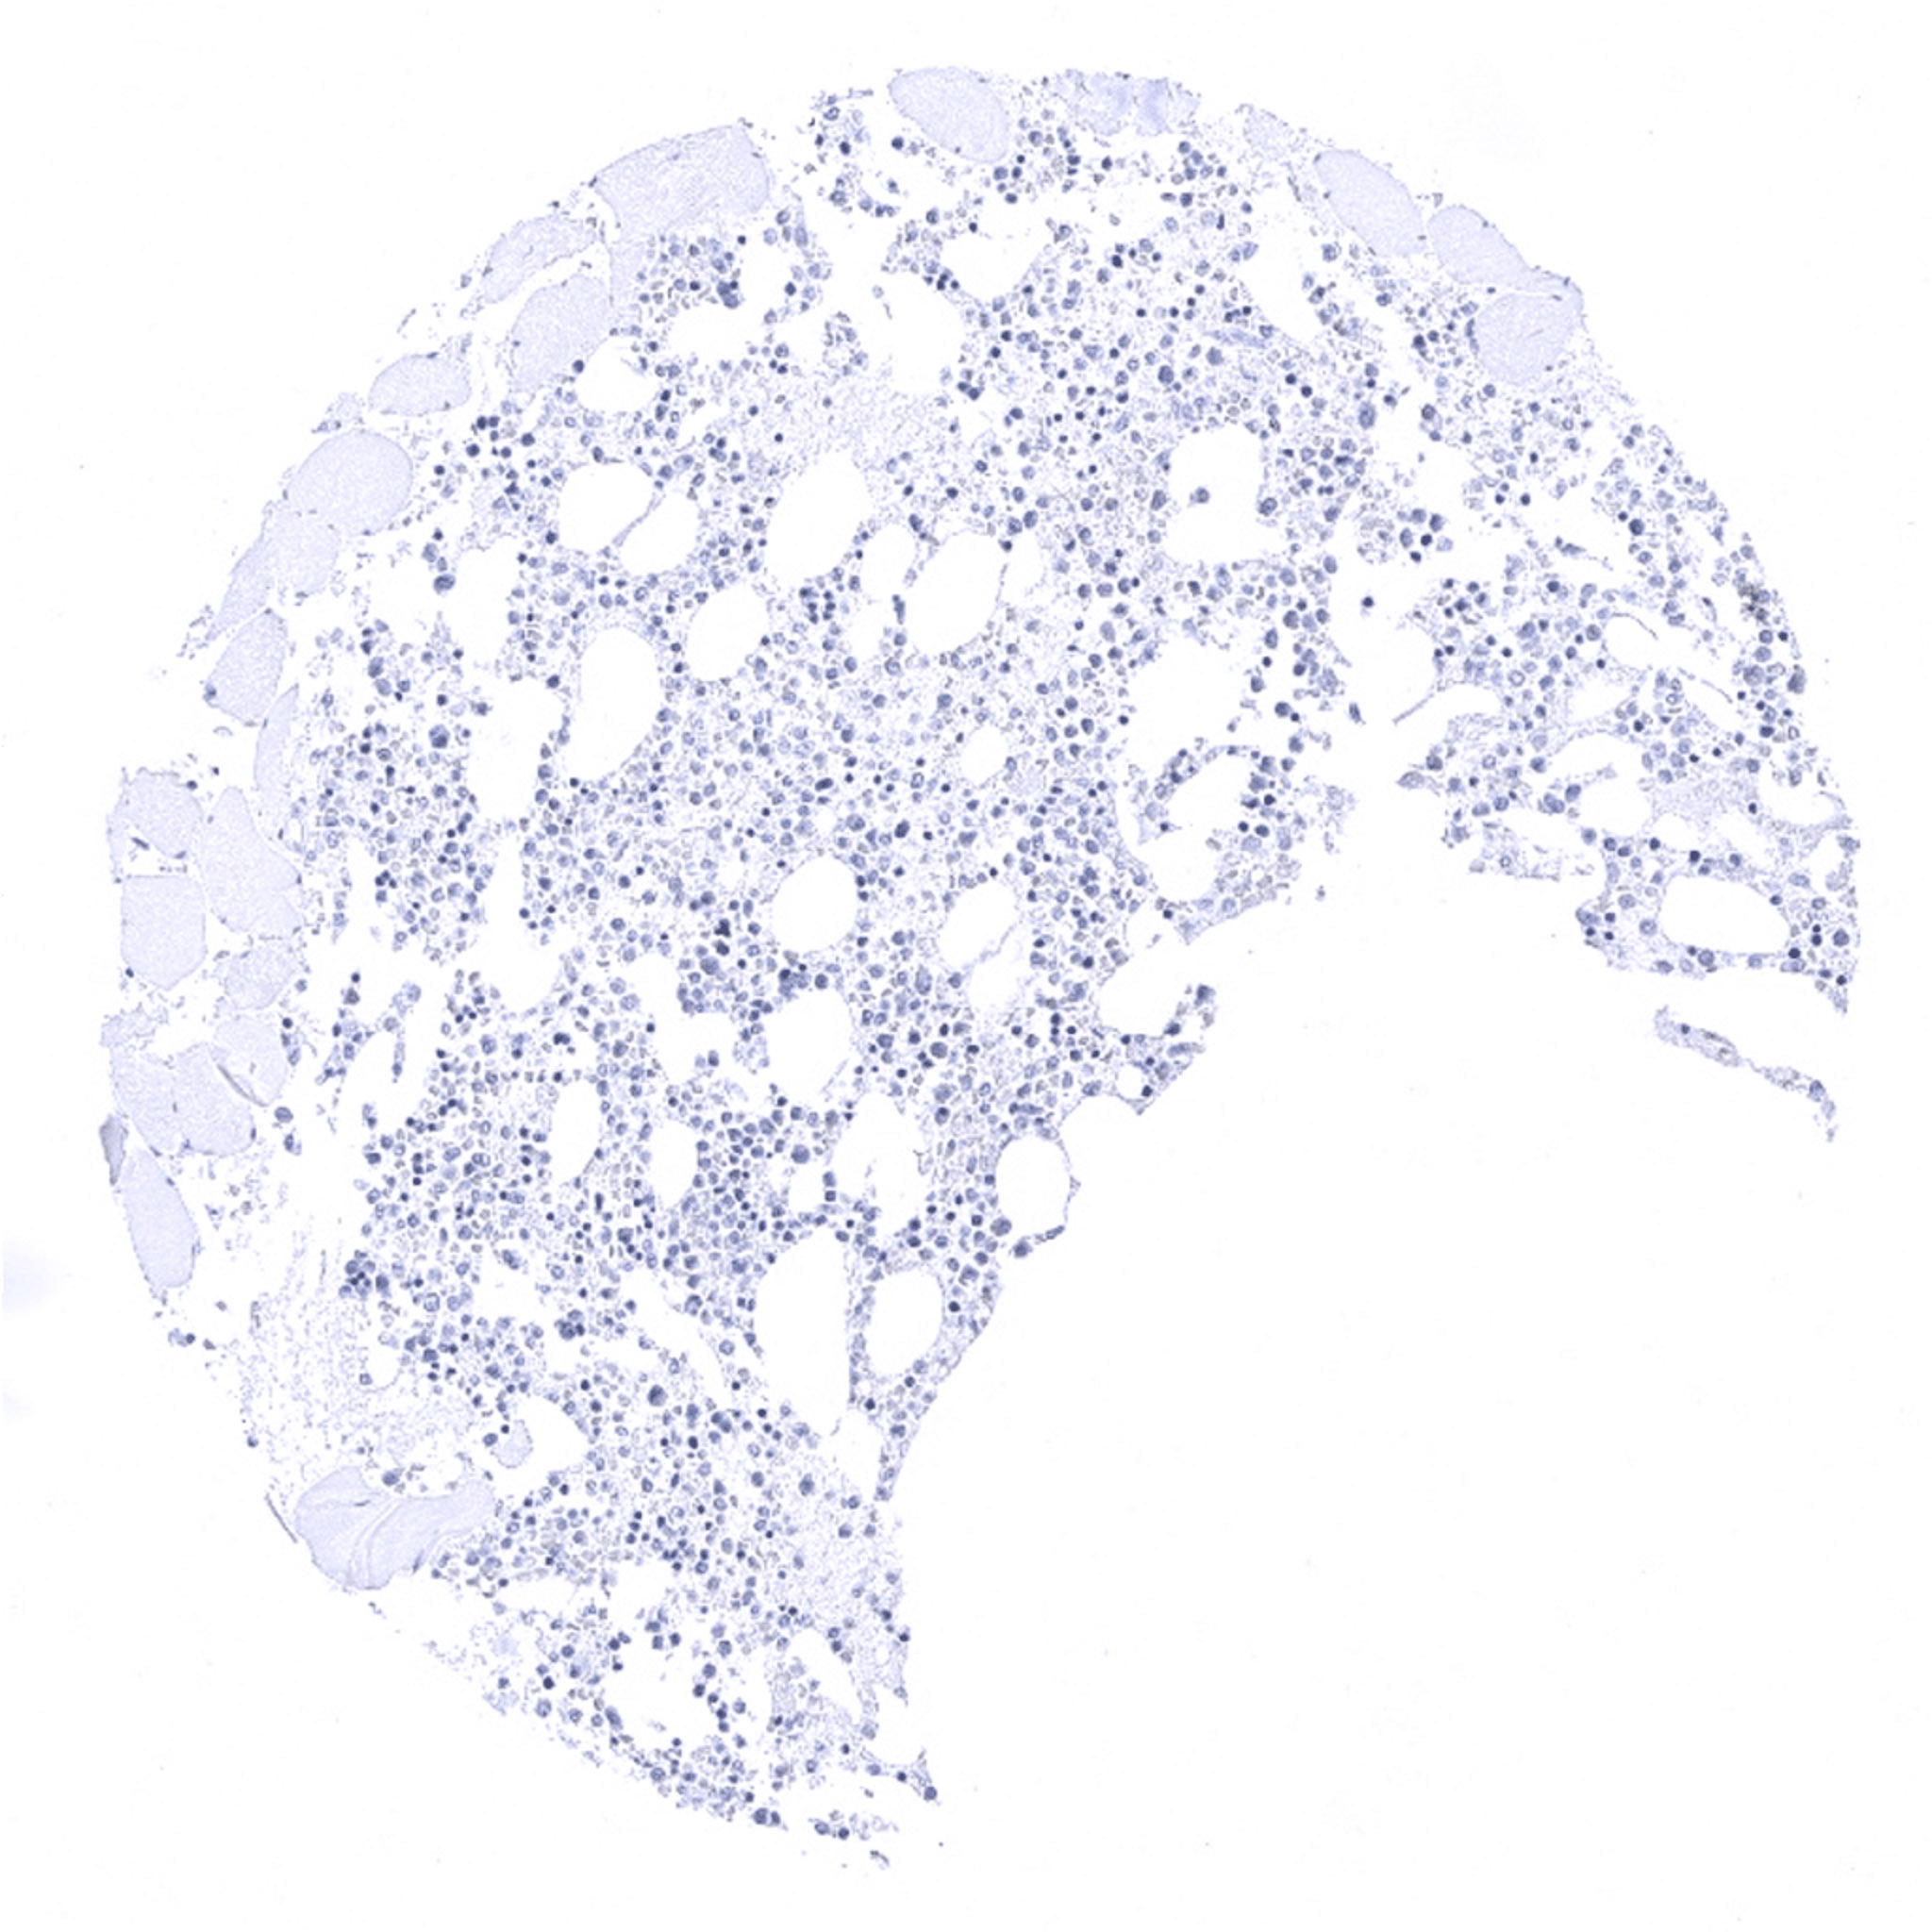

Pancreas – Positive NSE immunostaining of islets of Langerhans.